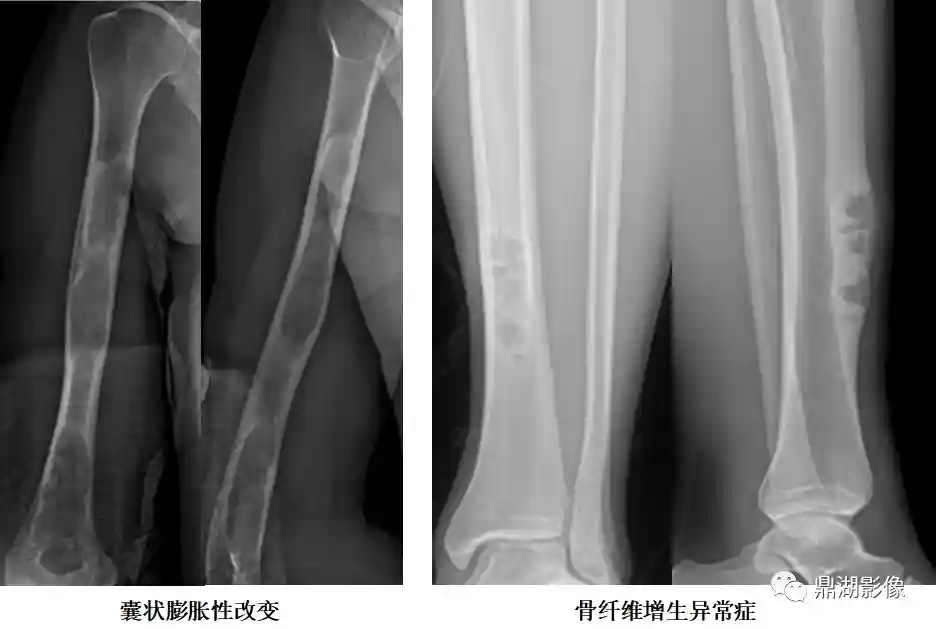

骨纤维异常增殖症

多发生在青少年,11―30岁为高发年龄

发生部位为一侧肢体的多数骨,以胫骨、股骨、颌骨较多见

囊状膨胀性改变:单囊或多囊,常有硬化边,内缘毛糙

磨玻璃样改变:指囊状膨胀性改变中的密度均匀增高如磨玻璃状

丝瓜瓢样改变:沿纵轴方向走形的粗大骨纹,颇似丝瓜瓤

地图样改变:单发或多发的溶骨性破坏,边缘锐利